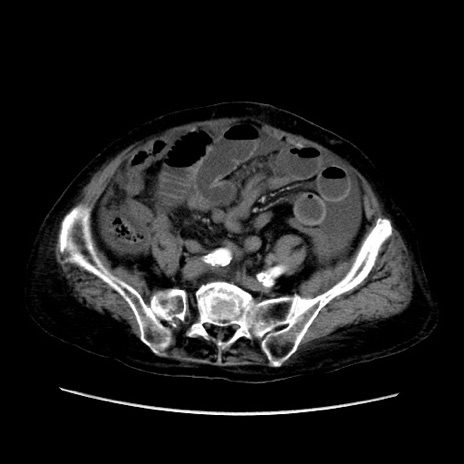

症例31(横断像)

【症例】80歳代 女性

【主訴】腹部膨満感

【現病歴】他院にて肝硬変にてフォロー中。1週間前から便秘、腹部膨満感、臍部腫瘤あり受診となる。

【既往歴】肝硬変

【身体所見】腹部膨隆あり、皮膚変化なし、疼痛なし。

【データ】WBC 4600、CRP 0.25